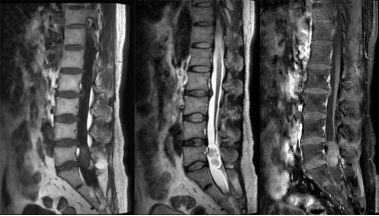

肿瘤位于硬脊膜外,类似于电缆的绝缘层与保护壳之间的位置。最常见的类型是转移性肿瘤(图8),但也可能出现如海绵状血管瘤或脂肪血管瘤等情况。这类肿瘤通常发展较快,病程相对较短。在早期阶段,患者可能会出现根性疼痛,并可能迅速进展至瘫痪;而感觉障碍(如麻木、感觉异常)可能出现并随病情进展加重。病变区域有时会有明显的压痛感。通过影像学检查,可以观察到椎体骨质受损以及椎旁软组织的变化。

图8.上胸段硬膜外转移瘤MRI图像